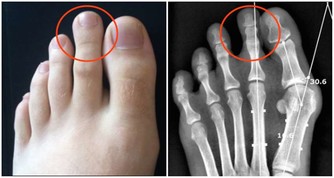

而且,目前磁療產品魚龍混雜,很難分辨是否安全。2017年,山東省便截獲了一批放射性超標嚴重的磁療保健床墊。經檢測,其年輻射劑量高達200毫西弗。

做一次X光檢查,受到的輻射量約是0.1毫西弗;簡單換算下,用這種床墊一年,等於拍了2000張X光片!